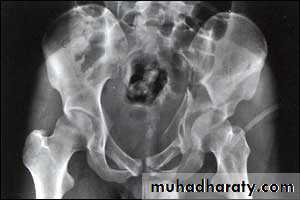

Central fracture -dislocation

Lower limbs